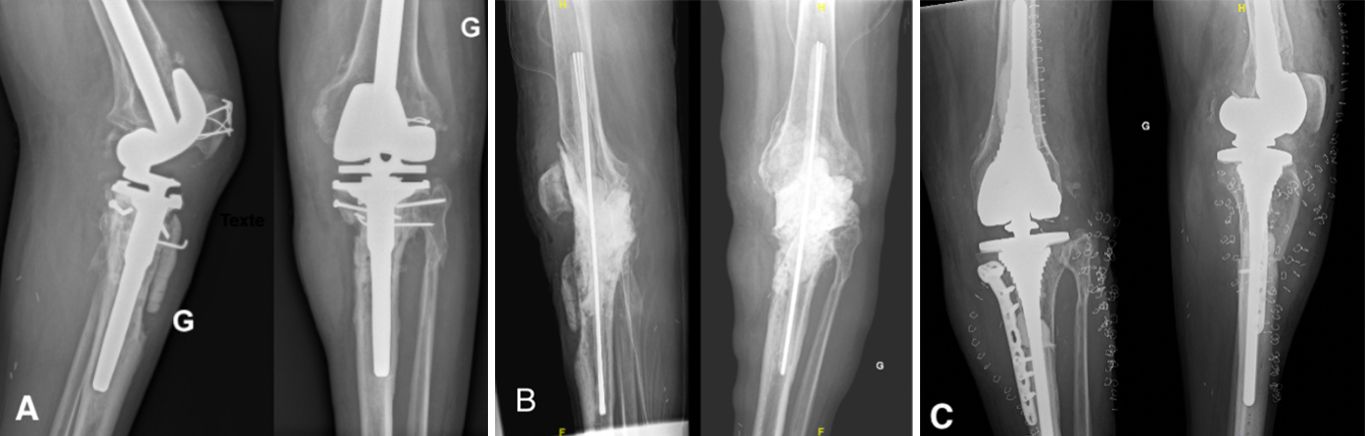

Antibiotic-impregnated cement spacers can be either static (non-articulating, block spacer) or dynamic [10]. Static spacers consist of a single block of cement inserted between the femur and the tibia (Case 1.B, 2.B, 3.B). It is non-articulating, fills the joint space and constitutes a temporary knee arthrodesis keeping the knee in full extension. This temporary immobilization leads amongst other things to joint stiffness and exposure difficulties at the time of reimplantation [9, 22, 23]. This increases the difficulty of prosthesis reimplantation and is associated with poorer clinical outcomes such as stiffness.

- Major bone loss, which is associated with a high risk of fracture, as well as a lack of fixation for a dynamic spacer (Cases 1-3).

- An incompetence of the collateral ligaments or the extensor mechanism, which can cause femoro-tibial dislocation with a dynamic spacer (Case 3).

Step 3: Making the static spacer

The firsts step is the fashioning of a rigid rod of cement reinforced by Kirschner wires to reduce the very high risk of spacer fracture. 3-4 wires of 2 mm diameter should be used and coated with high-viscosity antibiotic cement. When the mixture starts to solidify, it is molded manually by the surgeon (Fig.2).

The length must be long enough to have at least 6 cm of rod in each femoral and tibial canal, plus the length of the joint space to bypass the joint and be stable and strong enough. Once set, this rod, marked at its center, is introduced back and forth into the femoral and tibial canals until the center mark is at the midpoint of the joint space (Fig.3). We usually use 1 cement package of 40 g for this rod.

Next, the whole spacer is prepared using high-viscosity antibiotic cement. We use cement with Gentamycin and add crystalline Vancomycin, 1g per cement package. The Vancomycin should be added to the cement before being added to the liquid monomer [13]. If the Vancomycin is added later, the mixing is inconsistent due to poor dissolution and risks unequal diffusion into the soft tissues. We advise adding methylene blue to the preparation. We usually use 1 mL, added just at the start of mixing, to obtain a homogenous blue paste (Fig.4). The methylene blue is added to the cement to provide easy discrimination between native bone and cement and facilitate cement removal during the second stage of surgery [25].

The spacer should fill the joint space to maintain the native leg length. 2 minutes after the second cement mixture, the joint is opened with traction on the leg in extension to fill any bone defects and the joint space with cement. The size of the spacer should be appropriate but not too large to avoid excessive skin tension during wound closure. This second cementation stabilizes the construct and prevents spacer migration (Fig.5). The joint capsule, subcutaneous tissues, and the skin are closed in layers.